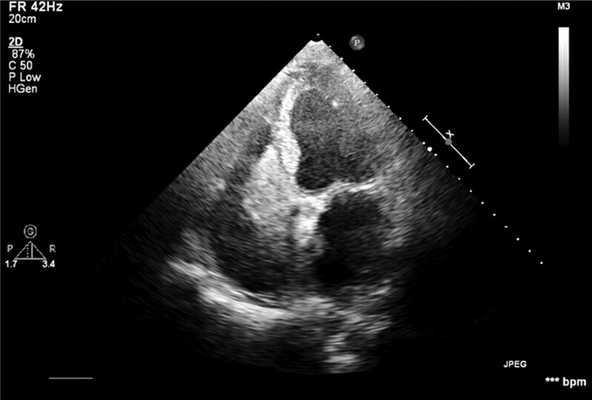

По результатам ЭхоКС выявлено увеличение левого предсердия (ЛП) до 4×5 см и 8×4,4 см, увеличение правого предсердия (ПП) до 6×5 см, отмечена дилатация правого желудочка (ПЖ). Выявлено гиперэхогенное образование, занимающее ¾ ПП и ПЖ, не связанное с межпредсердной перегородкой, создающее значительное препятствие притоку крови. Трикуспидальный клапан не дифференцирован, вероятно, за счет сдавления (рис. 1).

Рис. 1. Трансторакальная ультразвуковая картина опухоли (Philips iE33). Видно образование, занимающее большую часть правого предсердия и часть правого желудочка.